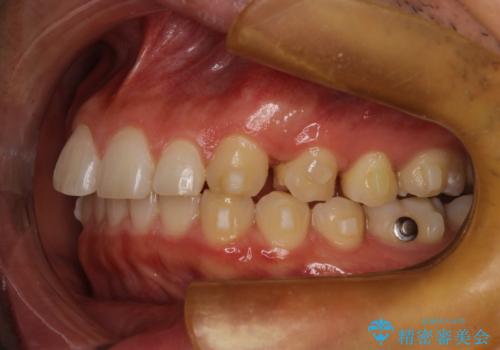

- 出っ歯を主訴に来院されました。

上の歯が全体的に下の歯の位置に比べると前方に位置しており、上の前歯が前方に傾斜している状態でした。

上の奥歯を後方に移動して、隙間を作り、前歯を引っ込める計画としました。